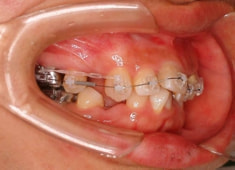

治療前